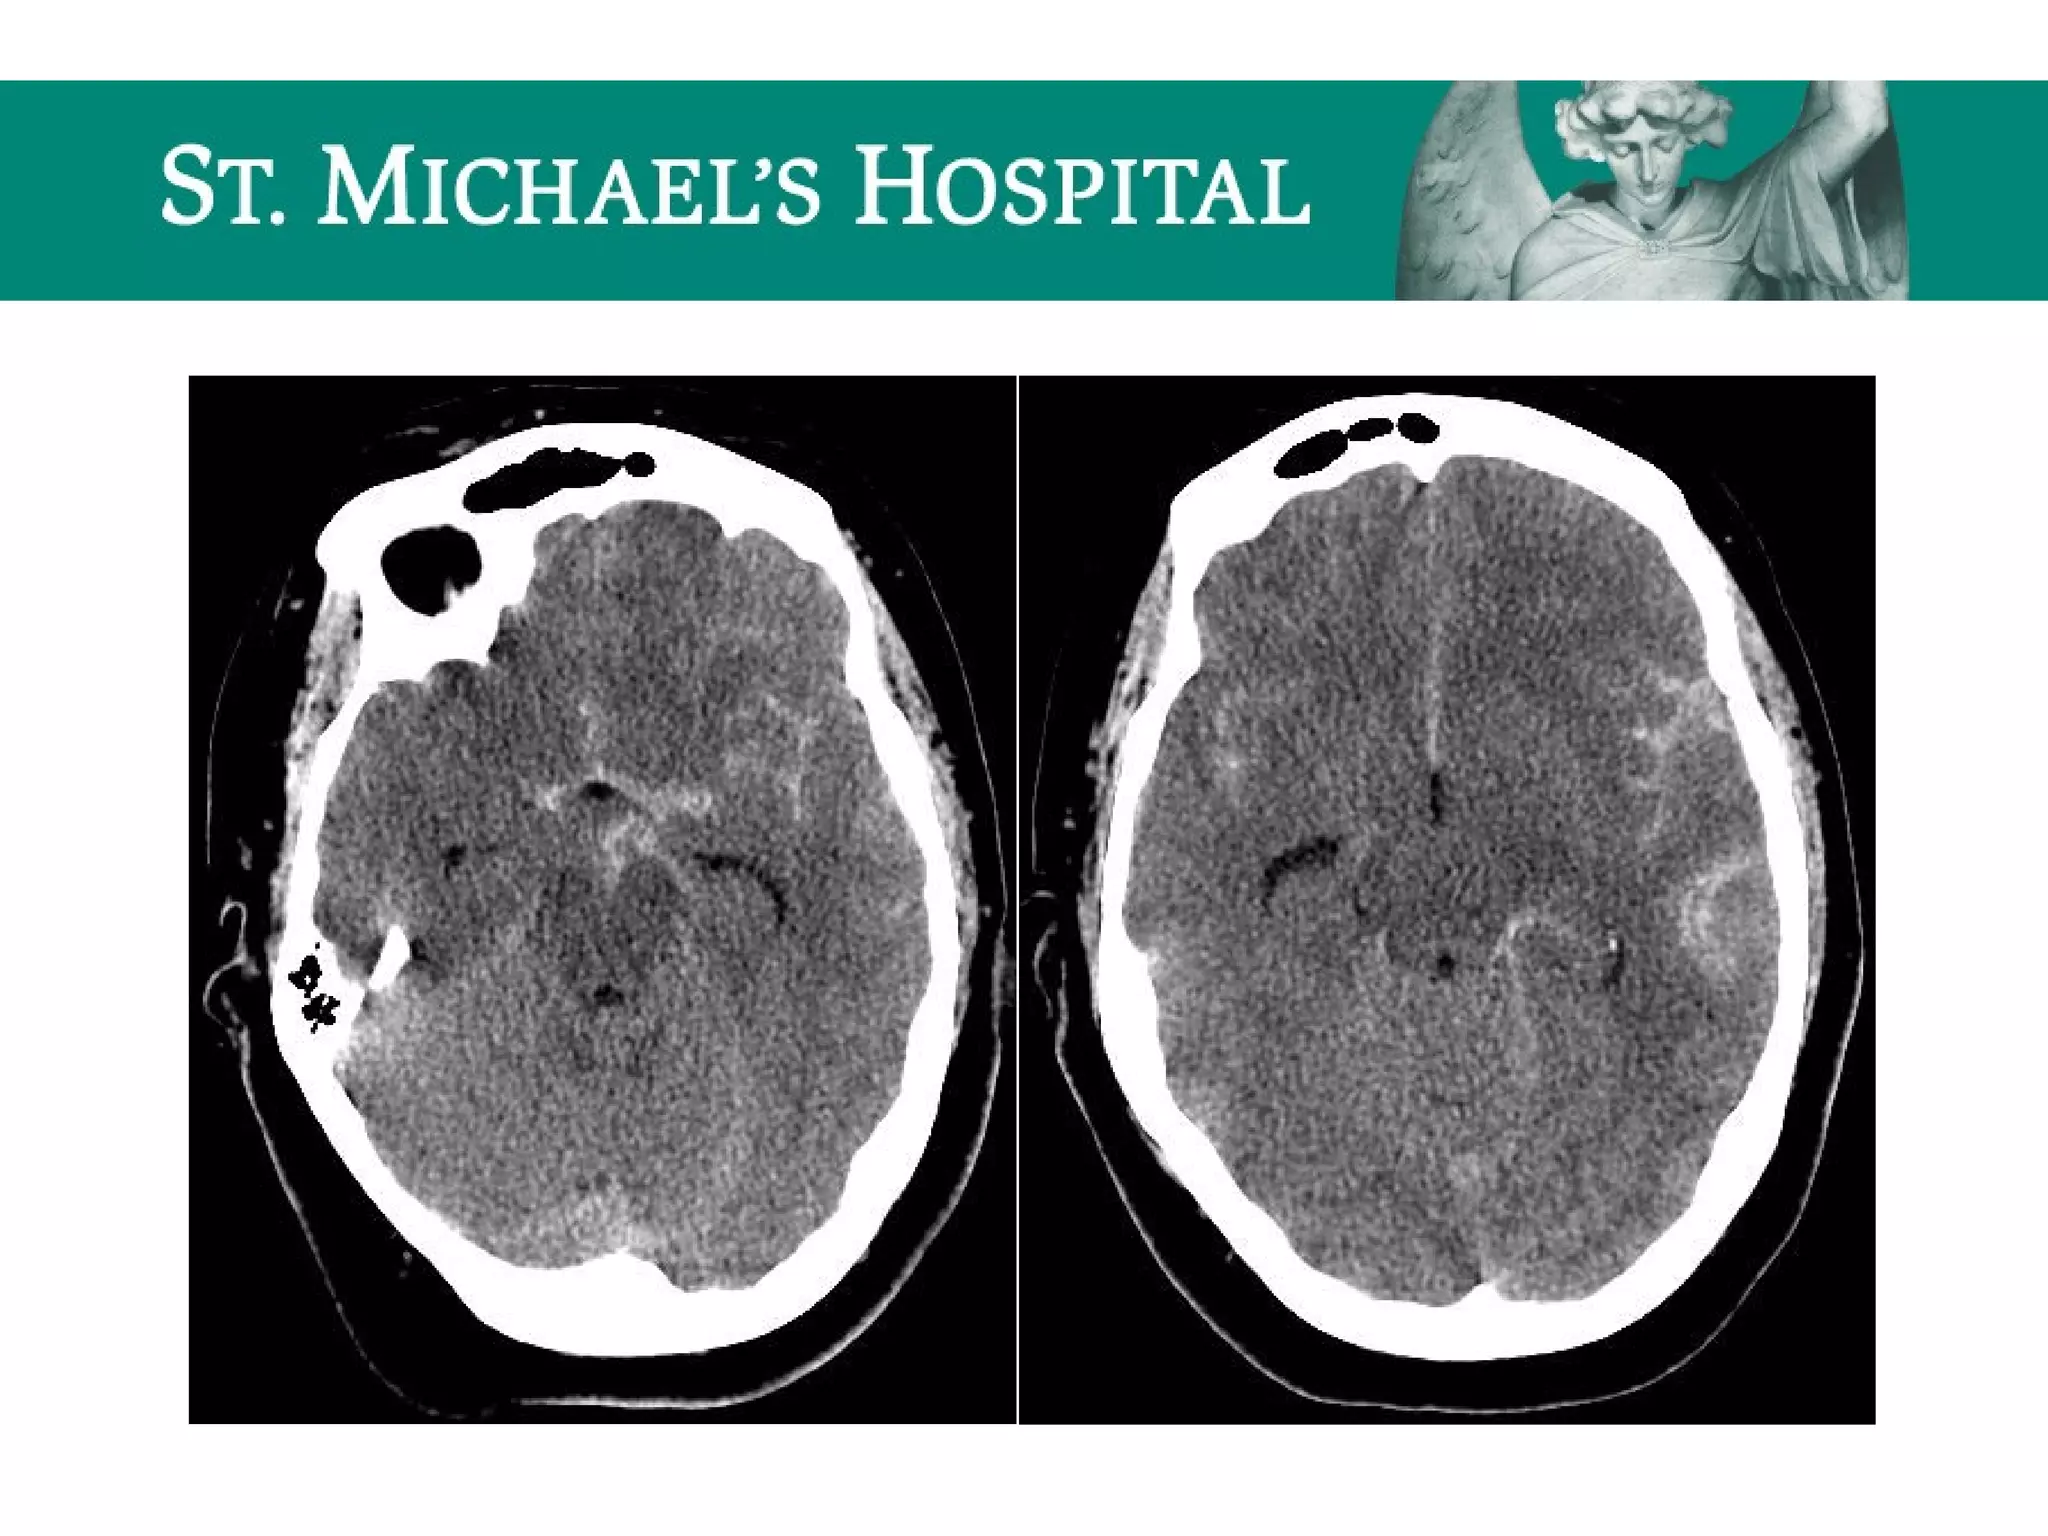

Cerebral Contusions

 Traumatic injury to cortical surface of brain

 Radiological features:

 Location:

– Often multiple, bilateral involving superficial cortex

– Frontal and temporal lobes > parietal, occipital, post. Fossa

– Coup and contra-coup injuries

 Unenhanced CT:

– Focal/multiple areas of high density (hemorrhage) with

surrounding low density (edema)